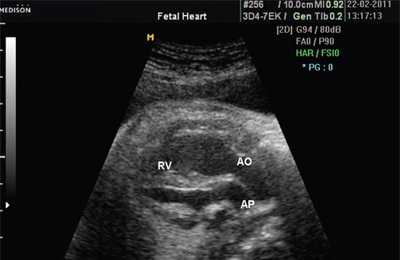

При эхокардиографии изучались четырехкамерный срез сердца плода (рис. 1) и срез через три сосуда (рис. 2). УЗИ проводилось трансабдоминальным датчиком, лишь при необходимости (затрудненная визуализация) использовался внутриполостной датчик. Четырехкамерный срез сердца плода при ультразвуковом сканировании трансабдоминальным датчиком визуализировался в 85% случаев, срез через сосуды - в 73%, при использовании трансвагинального датчика эти цифры существенно возрастали до 100 и 91% соответственно. Оптимизация пренатальной диагностики ВПС может быть достигнута путем строгого соблюдения основных методических правил. При оценке четырехкамерного среза плода необходимо оценить нормальное расположение сердца плода, исключив его эктопию (рис. 3), положение оси сердца плода, что не представляет никаких трудностей, нормальные пропорции и размеры камер сердца, движение створок атриовентрикулярных клапанов должно быть свободным, септальная створка трикуспидального клапана должна располагаться ближе к верхушке сердца (рис. 4). При оценке среза через три сосуда необходимо оценить взаиморасположение сосудов и их диаметр.

Рис. 1. Беременность 12 недель. Четырехкамерный срез сердца плода. Отчетливо видны камеры сердца.